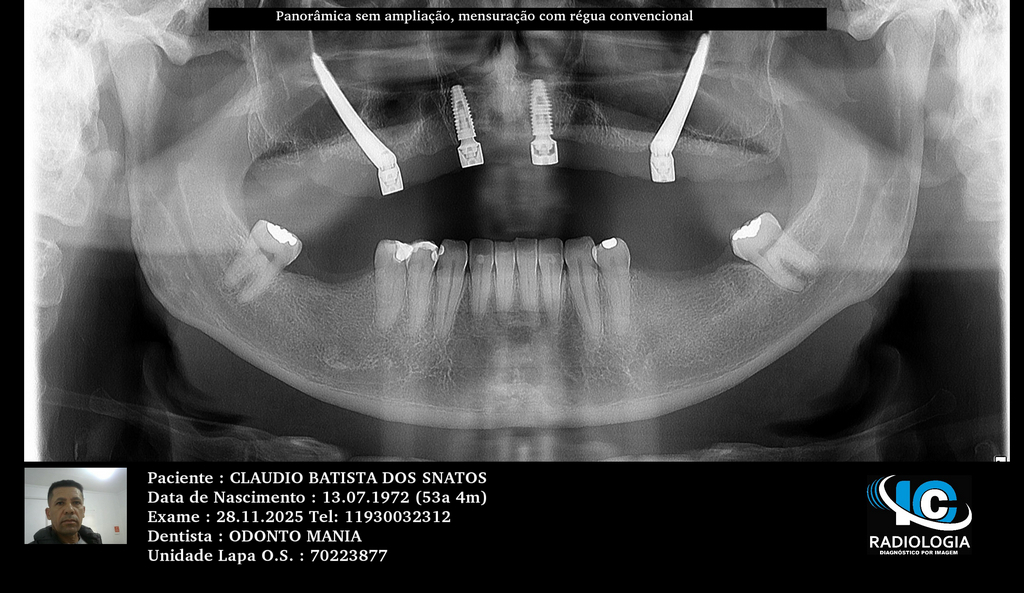

PRÓTESE TOTAL FIXA EM IMPLANTES

C.B.D.S.